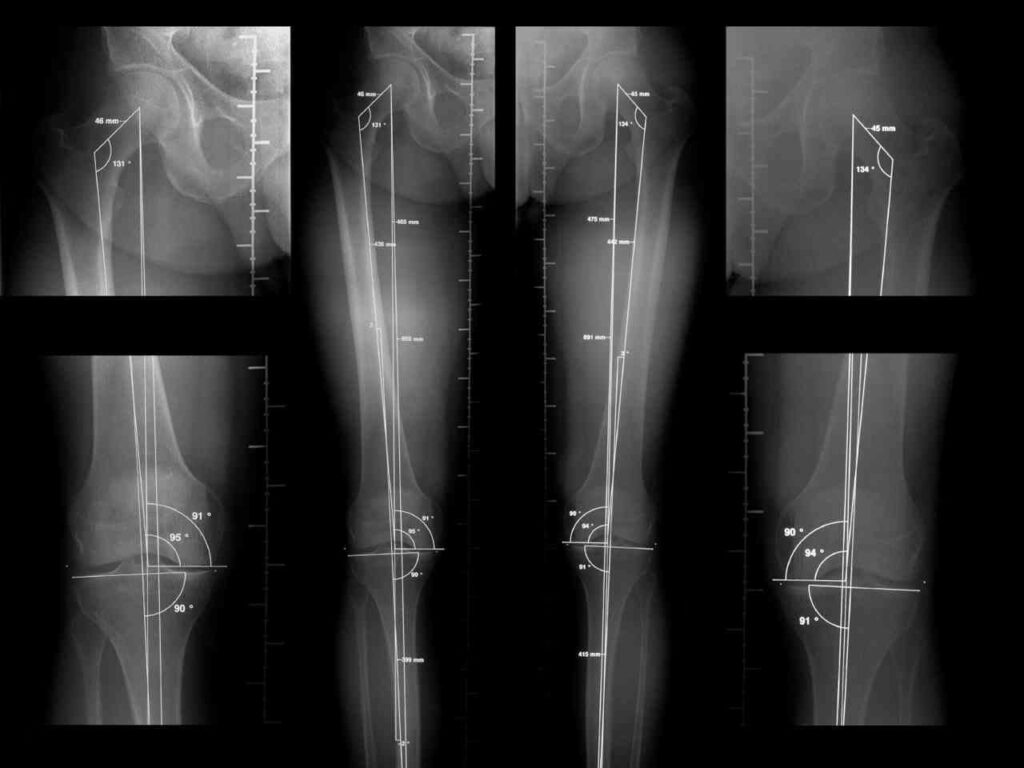

La telemetría de miembros inferiores, o telerradiografía, es un tipo específico de radiografía que se caracteriza por su amplio campo de visión. A diferencia de las radiografías estándar que suelen enfocarse en una articulación o segmento óseo particular, la telemetría captura una imagen completa que abarca desde las articulaciones de los tobillos hasta las caderas. Esta amplitud es esencial para evaluar la relación entre diferentes partes de la pierna y su alineación global.

La particularidad de esta radiografía es que se realiza con el paciente en posición de pie. Estar de pie es fundamental porque permite evaluar la alineación y la longitud de las piernas bajo la carga natural del peso corporal, que es la condición en la que las extremidades trabajan la mayor parte del tiempo. Esta posición revela cómo se distribuyen las fuerzas a través de las articulaciones y si existen desviaciones o discrepancias que no serían evidentes en una radiografía tomada en otra posición.

El equipo de radiografía captura una imagen panorámica de las extremidades inferiores. Debido a la longitud que debe cubrir la imagen, algunos equipos modernos realizan varias tomas secuenciales que luego son unidas digitalmente para crear una única imagen larga y continua. Este proceso asegura que se capture toda la longitud de los huesos largos (fémur y tibia) y su relación con las articulaciones principales (cadera, rodilla y tobillo).

2. Evaluar la alineación angular: La telemetría permite medir los ángulos que forman los huesos largos entre sí y con respecto a los ejes mecánicos y anatómicos. Esto es crucial para identificar desviaciones como el valgo (piernas en X) o el varo (piernas arqueadas). Estas angulaciones anormales pueden aumentar significativamente la carga sobre ciertas áreas de las articulaciones, llevando a su desgaste prematuro.